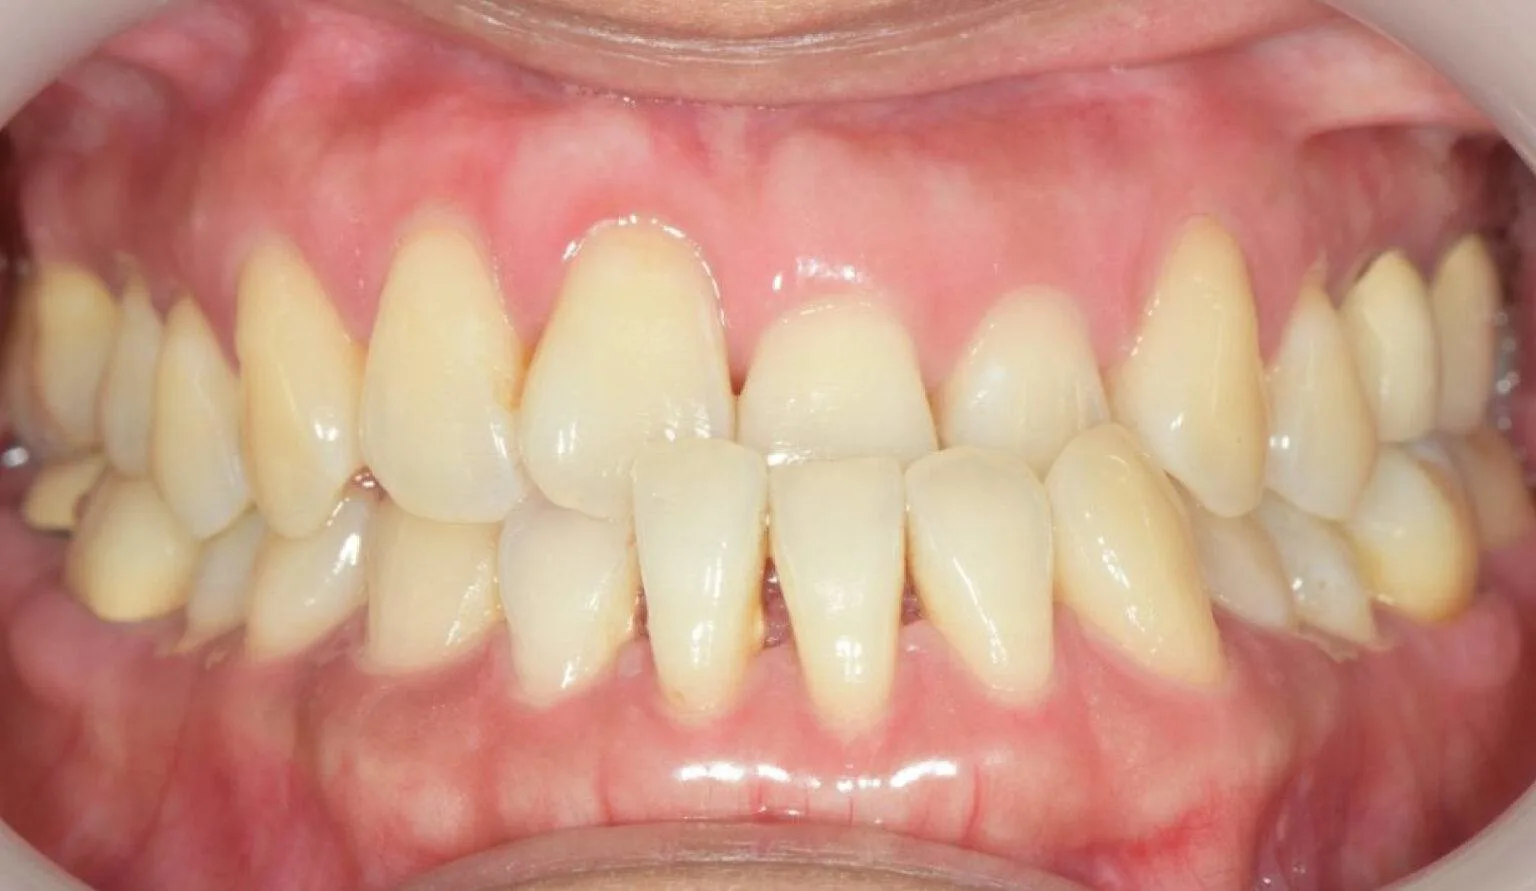

This is where the upper teeth horizontally protrude past the bottom teeth, also called an ‘Overbite’. A common dental complaint we hear that relates to protrusion is ‘my front teeth are sticking out’.

The protrusion of teeth can cause speech problems and make it difficult to consume food, this is due to the fact it can prevent correct biting and chewing.

Protrusion is a dental condition that is usually caused by skeletal issues with the lower jaw, mainly in those who have a growth deficiency. Overbites can cause irreparable soft tissue damage and also contribute to early tooth loss from excessive wear of the teeth. Besides overjets having functional side effects, they can also affect the aesthetics of the smile. Overall, it can look unpleasant to the eye, this can affect a person’s psychological and emotional state.

Protruded teeth commonly come in conjunction with patients with narrow arches, habits of tongue thrusting, swallowing and breathing improperly, phonetic problems – such as enunciating certain words and sounds like F and V, and allergies.